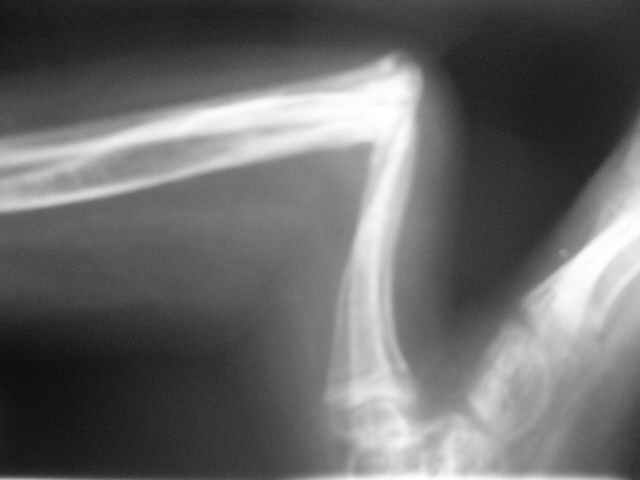

Уважаемые коллеги,Госпитализировали ребенка 4 лет с врожденной деформацией голени.

Нога опороспособна, безболезненна, выраженная хромота за счет укорочения.Признателен за рекомендации и высказанные мнения.Евгений И Чекашкин

Нога абсолютно опорна и безболезненна при осевой нагрузке и пальпации зоны деформации.